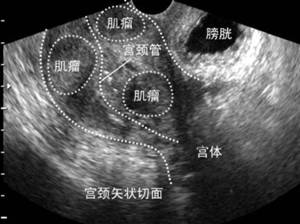

(图:子宫肌瘤超声影像)

另外,不同类型的子宫肌瘤对妊娠的影响也是有差异的,根据部位子宫肌瘤可以分为:粘膜下、肌壁间和浆膜下子宫肌瘤三种类型,如果把子宫想象成一个房间,在房间外发生的肌瘤就是浆膜下子宫肌瘤,房间内发生的肌瘤就是粘膜下子宫肌瘤,房间+墙壁内的则是肌壁间肌瘤。大多数学者认为浆膜下肌瘤基本不影响受孕,也不易导致流产,粘膜下肌瘤则与之相反,肌壁间肌瘤的影响取决于肌瘤的大小,较大的肌瘤(>5cm)可能不利于怀孕,较小的肌瘤则影响较小。

由此我们可以看出,拿到一份妇科超声报告时,需要关注的不仅仅是子宫肌瘤这个诊断,还应该详细调查有关肌瘤的部位、大小和数目的描述,简而言之,如果是粘膜下肌瘤或较大的肌壁间肌瘤(>5cm),因其对生育的不利影响,建议先处理肌瘤再考虑怀孕。大量的临床资料证实,肌瘤合并不孕的女性在子宫肌瘤切除术后,有一半以上能够自行怀孕。如果是浆膜下子宫肌瘤,或者较小的肌壁间肌瘤,可以先考虑怀孕。